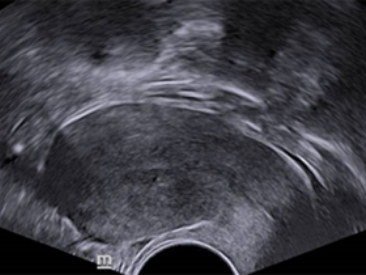

Klinik G?rĂŒntĂŒler